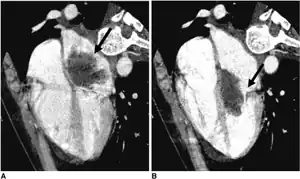

CT left atrial myxoma

In most cases, the diagnosis is based on clinical history, echocardiography, a CT scan or an MRI scan. Cardiac tumours are often first diagnosed after the patient has had a stroke, an embolism caused by detached tumour tissue.[8]